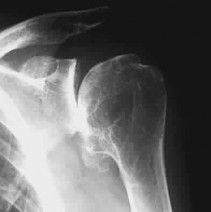

Question 81

A 65-year-old female sustains a 4-part proximal humerus fracture. Which of the following radiographic findings is the strongest predictor of ensuing humeral head ischemia according to Hertel criteria?